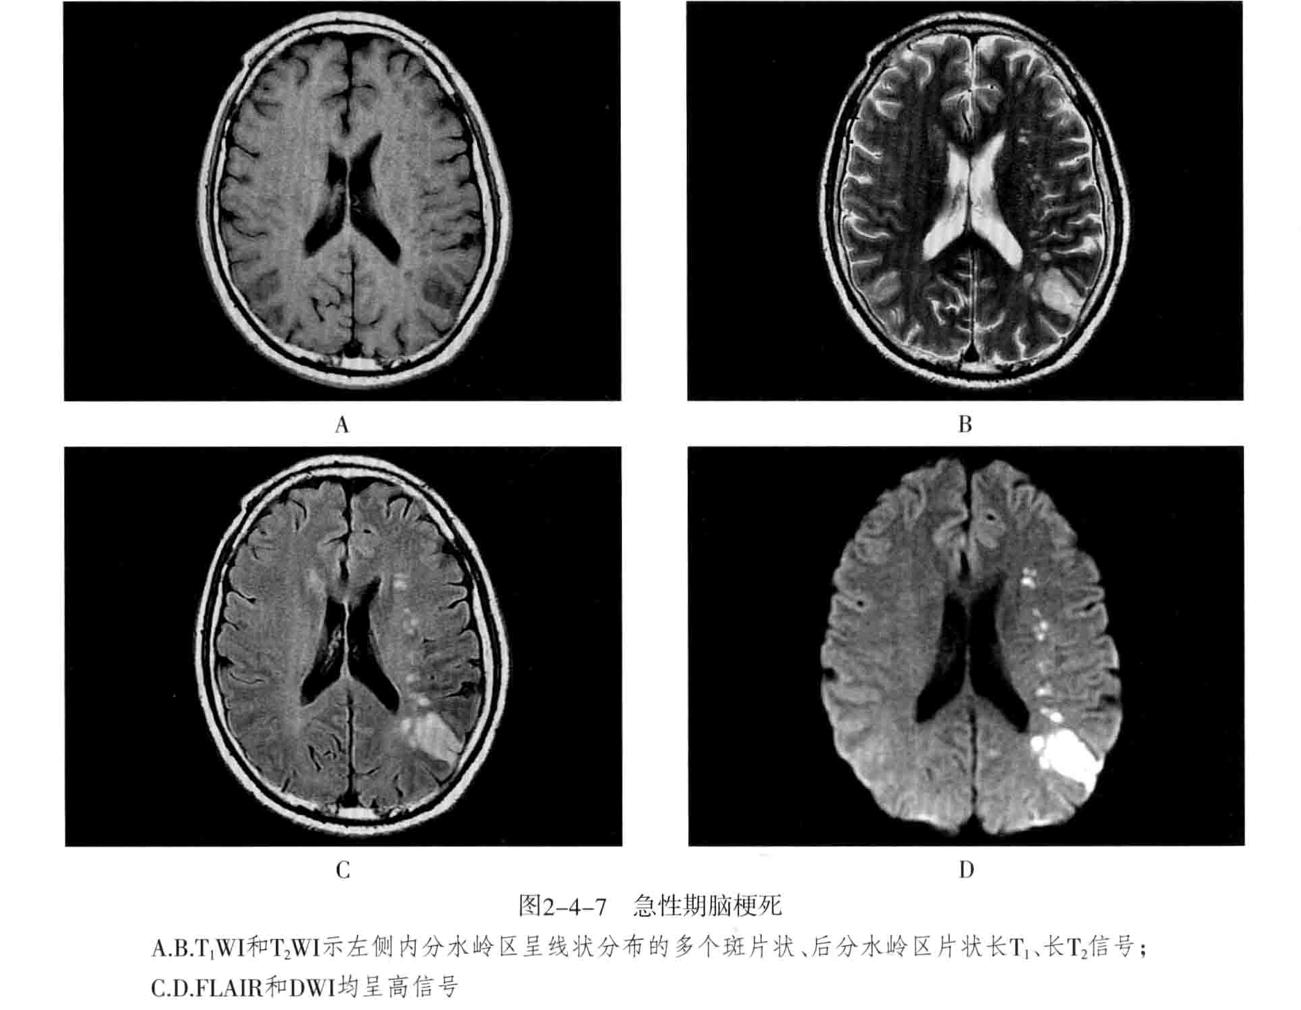

八、脑梗死:是一种缺血性脑血管疾病,常见有动脉闭塞性梗死和腔隙性脑梗死。主要病因为脑的大或中等管径的动脉发生粥样硬化,继发血栓形成,导致管腔狭窄、闭塞。以大脑中动脉闭塞最常见。脑梗死发生4-6小时脑组织发生缺血与水肿,继而脑组织出现坏死。1-2周后脑组织水肿逐渐减轻,坏死脑组织液化,梗死区出现吞噬细胞浸润,清除坏死组织,同时有胶质细胞增生和肉芽组织形成,8-10周后形成含液体的囊腔即软化灶。少数缺血性脑梗死在发病24-48小时后可因再灌注而发生梗死区内出血,转为出血性脑梗死。常见症状为偏瘫和偏侧感觉障碍、偏盲、失语等。

1. CT表现为脑组织内低密度灶,梗死后2-15天为脑水肿高峰期,此时可有脑水肿表现;梗死1个月以后,相邻部位的脑室、脑池或脑沟扩大,出现脑萎缩表现。增强后梗死区可出现不均匀强化,呈脑回状、条状、环状或结节状强化。梗死区强化是由于血脑屏障破坏、新生毛细血管和血液灌注过度所致。

2. MRI在脑梗死6小时之内,由于细胞毒性水肿,DWI可发现高信号,此后发生血管源性水肿、细胞死亡、髓鞘脱失、血脑屏障破坏,T1与T2弛豫时间延长。梗死后期,小的病灶不显示,表现为脑萎缩,大的病灶表现为软化灶。